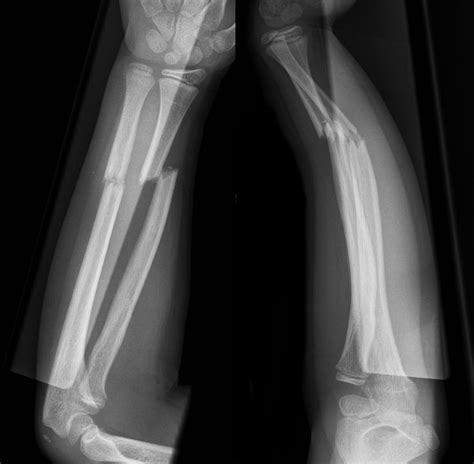

• Imaging Tests: X-rays are the primary diagnostic tool for identifying fractures. In some cases, additional imaging tests like CT scans or MRIs may be required for a more detailed view.

Imaging tests are crucial for determining the type and severity of the fracture, which will guide the treatment plan.

• Midshaft Ulna Fracture: Occurs in the middle of the ulna.